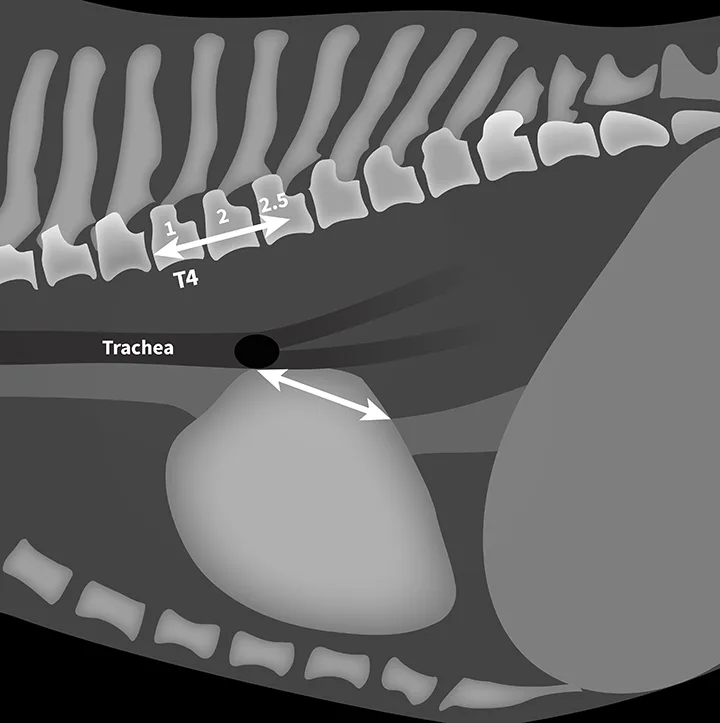

FIGURE 1

VLAS measurement in a dog with suspected stage B1 MMVD using a left lateral radiograph (A). A caliper was used to measure from the center of the most ventral aspect of the carina to the most caudal aspect of the left atrium, where it intersects with the dorsal border of the caudal vena cava. This measurement was transferred to the cranial aspect of T4 and extended caudally along the thoracic vertebrae. The number of vertebrae this line transversed was rounded to the nearest tenth to determine VLAS (2.1 VBUs). Stage B1 MMVD was confirmed via echocardiography. A redundant dorsal tracheal membrane, gastric food/foreign material, and mild T3 to T4 spondylosis deformans can also be seen. An orthogonal radiograph of the patient provides a more complete evaluation of cardiac silhouette (B); normal location of the left atrium is indicated (circle).

FIGURE 2

VLAS measurement in a dog with suspected stage B2 MMVD using a right lateral radiograph (A). A caliper was used to measure from the center of the most ventral aspect of the carina to the most caudal aspect of the left atrium, where it intersects with the dorsal border of the caudal vena cava. This measurement was transferred to the cranial aspect of T4 and extended caudally along the thoracic vertebrae. The number of vertebrae this line transversed was rounded to the nearest tenth to determine VLAS (2.8 VBUs). Stage B2 MMVD was confirmed via echocardiography. Other structures are unremarkable. An orthogonal radiograph of the patient provides a more complete evaluation of cardiac silhouette (B); normal location of the left atrium is indicated (circle).